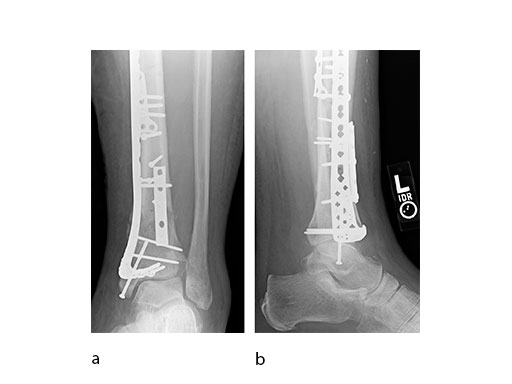

Case 3: Horse fall (Case provided by Mark Lee, Sacramento, USA)

A 45-year-old patient fell from his horse, receiving a closed bimalleolar fracture/ dislocation (Fig 10). Computed tomorgraphy demonstrated an additional anterolateral avulsion injury and syndesmosis dislocation. Osteosynthesis was conducted with a VA-LCP Lateral Distal Fibula Plate.

Push technique was required to achieve fibular reduction, and the syndesmosis was reduced and clamped with periarticular clamps (Fig 11). Postoperative x-rays at 4 weeks demonstrated good maintenance of reduction (Fig 12).